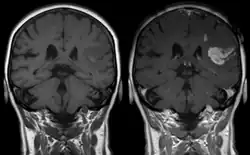

| T1 MRI of an ischemic stroke in the brain without (left) and with (right) contrast. | |

Diagnosis of a cerebral vascular accident begins with a general neurological examination, used to identify specific areas of resulting injury. A CT scan of the brain is then used to identify any cerebral hemorrhaging. An MRI with special sequences called diffusion-weighted MR imaging (DWI), is very sensitive for locating areas of an ischemic based stroke, such as a watershed stroke.